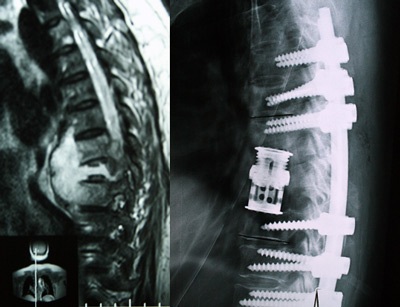

Cột sống của bệnh nhân L.K.L trước và sau phẫu thuật. |

Cả 22 ca cột sống lần này đều rất nặng như trường hợp của bệnh nhân L.K.L (55 tuổi). Hai tháng trước mổ, bà L. đau lưng và liệt hoàn toàn 2 chân kèm bí tiểu, được điều trị tại BV Đại học Y dược, sau đó chuyển sang Khoa cột sống A, bệnh viện CTCH.

Chẩn đoán khi nhập viện là lao cột sống N7 - N8 kèm liệt hoàn toàn 2 chân và bí tiểu, được điều trị kháng lao và phẫu thuật ngày 8/5.

Sau phẫu thuật 1 ngày, bệnh nhân đã phục hồi vận động nhóm cơ ở cổ bàn chân, 3 hôm sau phục hồi vận động được đến gối và 2 bên háng. Sau 1 tuần, bệnh nhân đã có thể duỗi và gập 2 chân tuy còn yếu nhưng nhiều khả năng phục hồi vận động hoàn toàn và phục hồi đường tiểu. Ca bệnh này được miễn giảm tiền dụng cụ thân đốt sống giả có giá khoảng 64 triệu đồng.